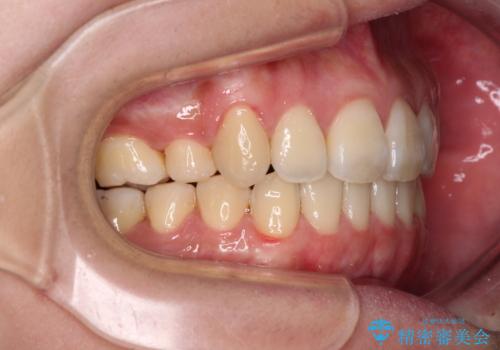

- 八重歯と叢生を気にして来院された患者様です。

上下の前歯が非接触であり、叢生や八重歯が顕著であったため、上顎左右第一小臼歯2本を抜歯して排列することとしました。

抜歯により移動量が多くなるため、ワイヤーや補助装置を活用し、その後インビザラインによる矯正治療を行うこととしました。

元々奥歯に負担のかかる咬み合わせですり減っていたため、仕上がった歯並びでも奥歯が咬んでいないように見えましたが、実際にはしっかりと咬合しており、患者様本人も咬んだ感触に違和感はないとのことでした。